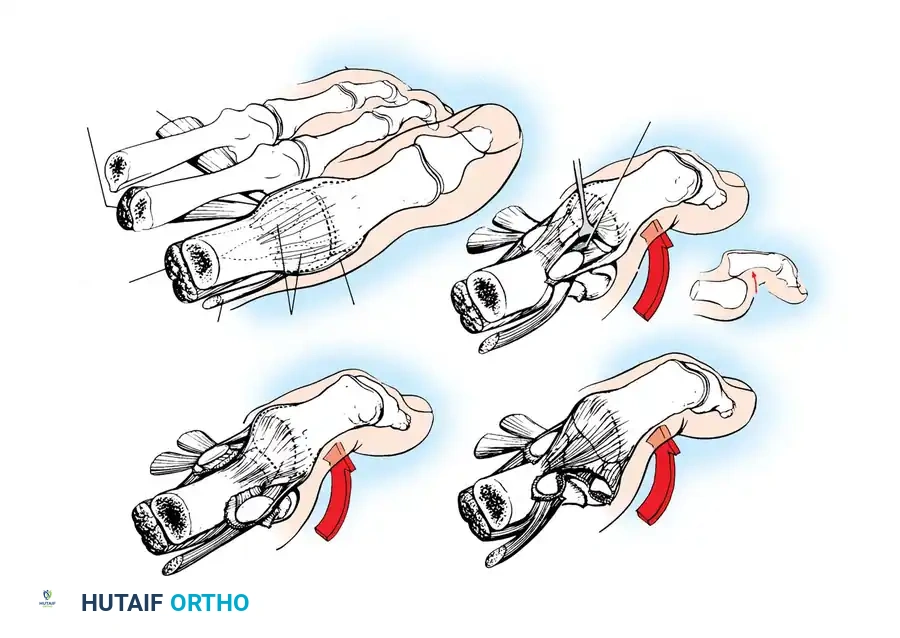

Technique 86-19: Sesamoidectomy

- Incision and Exposure: Make a medial longitudinal incision centered just plantar to the midline of the first MTP joint. Incise the capsule longitudinally in line with the skin.

- Joint Evaluation: Evaluate the intraarticular portion of the sesamoid to assess cartilage quality and fragment mobility. Inspect the plantar surface of the first metatarsal head for corresponding chondral damage.

- Nerve Protection: Approach the sesamoid via an extracapsular route. It is critical to identify and protect the proper medial plantar nerve to the hallux, which emerges plantarly at the musculotendinous junction of the abductor hallucis muscle. Gently retract this nerve plantarly.

- Excision: Make an incision directly over the sesamoid. Perform either a complete enucleation or a partial excision of the fragmented/necrotic portion.

- FHB Repair (Critical Step): The defect in the flexor brevis mechanism must be robustly repaired. Use a 2-0 nonabsorbable polyethylene suture. If a partial excision was performed, use a 0.045-inch K-wire to drill holes in the remaining sesamoid fragment, securing the FHB tendon directly to the bleeding cancellous surface.

- Closure: Repair the joint capsule with 2-0 absorbable sutures and close the skin with nylon.

Technique 86-20: Autogenous Bone Grafting (Anderson and McBryde)

- Incision: Make a 5-cm longitudinal skin incision along the medial plantar aspect of the first ray, centered over the MTP joint.

- Capsular Approach: Identify the capsule and abductor hallucis tendon. Divide them in line with the skin incision, entering the joint dorsal to the tibial sesamoid.

- Articular Inspection: Retract the tissues to expose the articular surface of the sesamoid. If severe cartilaginous destruction is present, abort the grafting procedure and proceed with excision. If the cartilage is intact, proceed with extraarticular bone grafting.

- Extraarticular Exposure: Dissect plantar to the abductor hallucis tendon to expose the plantar aspect of the tibial sesamoid. Strictly avoid injury to the plantar digital nerve.

- Preparation of the Nonunion: Following sharp periosteal elevation, identify the nonunion site. Gross motion is often palpable. Using a small dental curet, meticulously debride all fibrous and necrotic tissue from the nonunion interface without violating the dorsal articular cartilage. (Send debrided tissue for histological examination).

- Graft Harvesting and Placement: Harvest cancellous autogenous bone graft locally through a small cortical window created in the medial eminence of the first metatarsal head. Pack this graft tightly into the sesamoid defect. The intact tendinous expansion surrounding the sesamoid usually provides sufficient stability, keeping the fragments in close apposition without the need for internal hardware.

- Closure: Meticulously approximate the periosteal layers and close the wound with absorbable sutures.